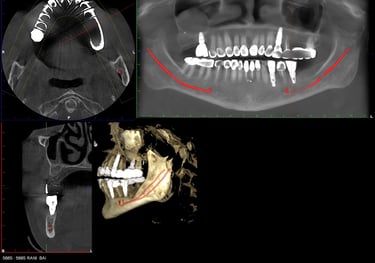

Dental Implants

A long-term solution for missing teeth. Dental implants restore function, appearance, and confidence with a natural-looking, stable result.